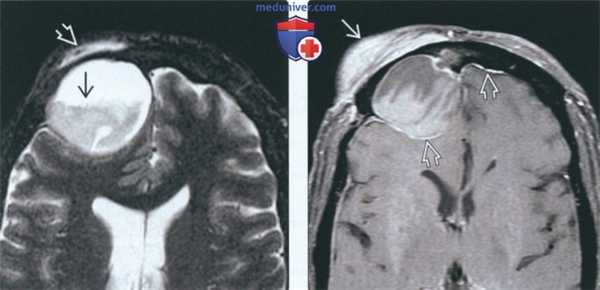

(Слева) На аксиальной КТ в костном окне определяется мукоцеле задних ячеек решетчатой пазухи, распространяющееся в сфеноидальные пазухи, но не в глазницу. Костная пластинка на периферии мукоцеле истончена и видоизменена.

(Справа) На корональной КТ в костном окне в правой верхнечелюстной пазухе (нетипичная локализация) определяется мукоцеле большого размера, приводящее к обструкции полоаи носа. Обратите внимание на признаки хронического левоаороннего гайморита: уменьшение объема пазухи и утолщение ее стенок.

(Слева) На аксиальной МРТ (Т2 ВИ FS) определяется большое мукоцеле правой лобной пазухи с уровнем «жидкость-жидкость» и компонентами с различной интенсивноаью сигнала. Мукоцеле распрсктраняется в поверхностные мягкие ткани, приводя к отеку.

(Справа) На аксиальной MPT (Т1 ВИ FS) у этого же пациента определяется отек и контрааное усиление поверхностных мягких тканей над разорвавшимся мукоцеле. Контрастирование твердой мозговой оболочки в передней черепной ямке сопоставимо с ранними воспалительными изменениями.